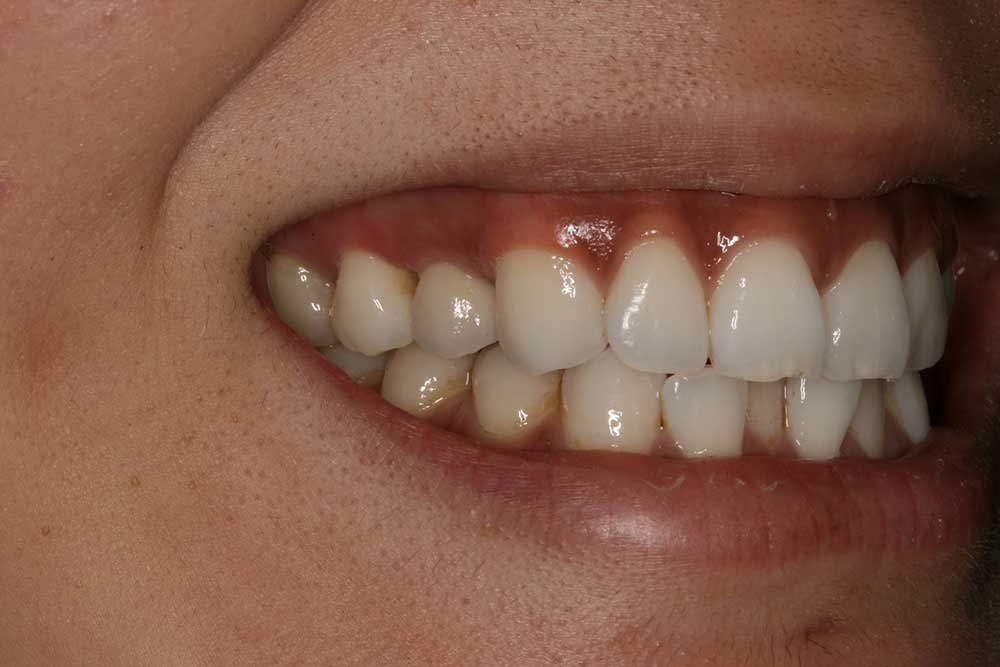

Corey E.

This patient had lost his front tooth due to an accident and had an Implant placed to replace it.